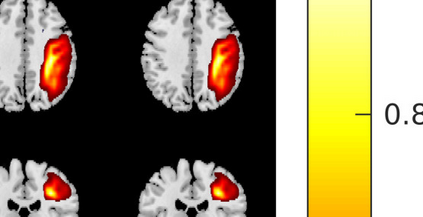

In the last two decades, unsupervised latent variable models---blind source separation (BSS) especially---have enjoyed a strong reputation for the interpretable features they produce. Seldom do these models combine the rich diversity of information available in multiple datasets. Multidatasets, on the other hand, yield joint solutions otherwise unavailable in isolation, with a potential for pivotal insights into complex systems. To take advantage of the complex multidimensional subspace structures that capture underlying modes of shared and unique variability across and within datasets, we present a direct, principled approach to multidataset combination. We design a new method called multidataset independent subspace analysis (MISA) that leverages joint information from multiple heterogeneous datasets in a flexible and synergistic fashion. Methodological innovations exploiting the Kotz distribution for subspace modeling in conjunction with a novel combinatorial optimization for evasion of local minima enable MISA to produce a robust generalization of independent component analysis (ICA), independent vector analysis (IVA), and independent subspace analysis (ISA) in a single unified model. We highlight the utility of MISA for multimodal information fusion, including sample-poor regimes and low signal-to-noise ratio scenarios, promoting novel applications in both unimodal and multimodal brain imaging data.